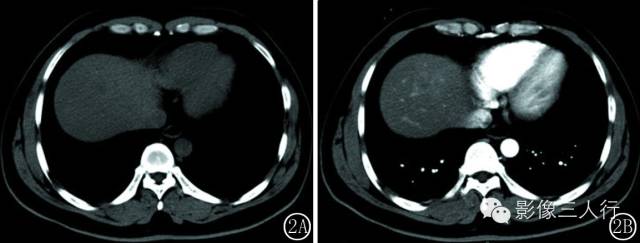

图 2 厚壁环形强化型 IPL 。 图 2A平扫病灶边界不清 ,低密度为主 。 图 2B 动脉期 ,病灶边缘明显环形强化 。 图 2C 延迟期 ,病灶呈厚壁全瘤强化 ,中心见条片状低密度不强化区